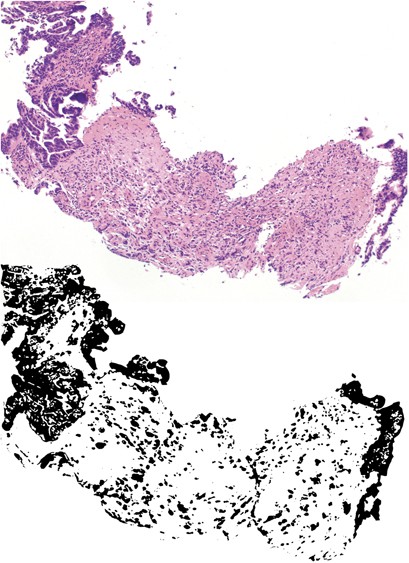

Peri-tumoral budding was scored in analogy to the method proposed by Nakamura et al.22 Tumor budding at the invasive tumor front in the resection specimen, namely peri-tumoral budding, was designated as ‘high peri-tumoral budding’ when at least one focus of high tumor budding was detected at the entire invasive front at low magnification ( × 2.5 objective, 10 × 20 mm field of view eye piece, Zeiss Axioscope, Germany) and ‘low’ budding, ie, cases where tumor budding was not detected at low power magnification, with occasional budding at intermediate magnification × 10, difficult to find or absent. For intra-tumoral budding in the biopsy specimens, the same criteria were applied as for peri-tumoral budding, ie, being obvious at low power and being confirmed at intermediate power magnification. Tumor budding is illustrated in Figures 1 and 2. Thirty-nine resection specimens and 14 biopsy cases were evaluated by a second pathologist (SC) to assess the inter-observer agreement of the scoring method blinded to other data.

Biopsy specimen with high intra-tumoral budding in H&E staining (top); extracted epithelial component from immunohistochemical staining for cytokeratin for the purpose of illustration (bottom).